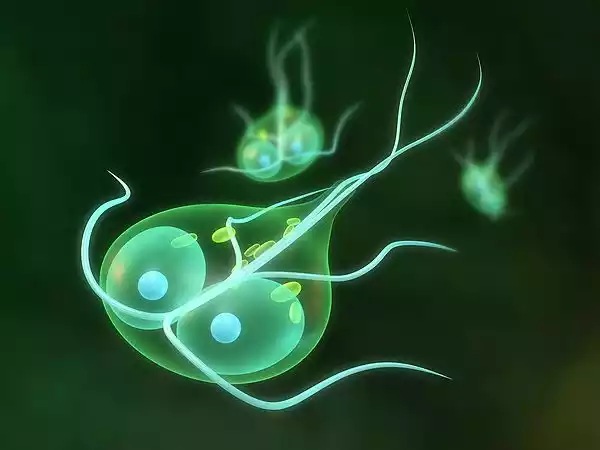

Giardia is a genus of microscopic, flagellated protozoan parasites that can infect the digestive systems of various animals, including humans. Giardia duodenalis, formerly known as Giardia lamblia or Giardia intestinalis, is the species most commonly associated with human infections.

- Flagellated Organisms: Giardia parasites possess hair-like structures called flagella, which they use for movement and attachment to the host’s intestinal lining.

- Two Morphological Forms: Giardia alternates between two forms in its lifecycle: the dormant cyst form, which is resistant to environmental conditions, and the active trophozoite form, which is found within the host’s intestine.

- Excystation: In the host’s stomach and small intestine, the cysts release trophozoites, which are the active, motile forms of Giardia.

- Attachment and Replication: Trophozoites attach to the intestinal lining using their adhesive discs and reproduce through binary fission, where a single organism divides into two.

- Encystation: As trophozoites move further down the intestine, they transform back into cysts, allowing them to survive outside the host’s body.